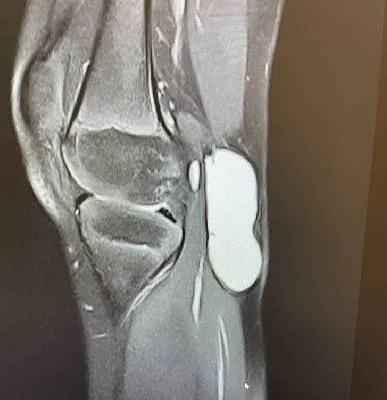

The wrist is a highly flexible and complex joint that supports hand movement and daily activities.

I went for wrist pain and Dr. Haytham Elkhatib Orthopedic treated me with utmost care and

professionalism. Even taking extra time to explain to me the diagnosis in simple terms .

Thank you so much Dr. Haytham ·